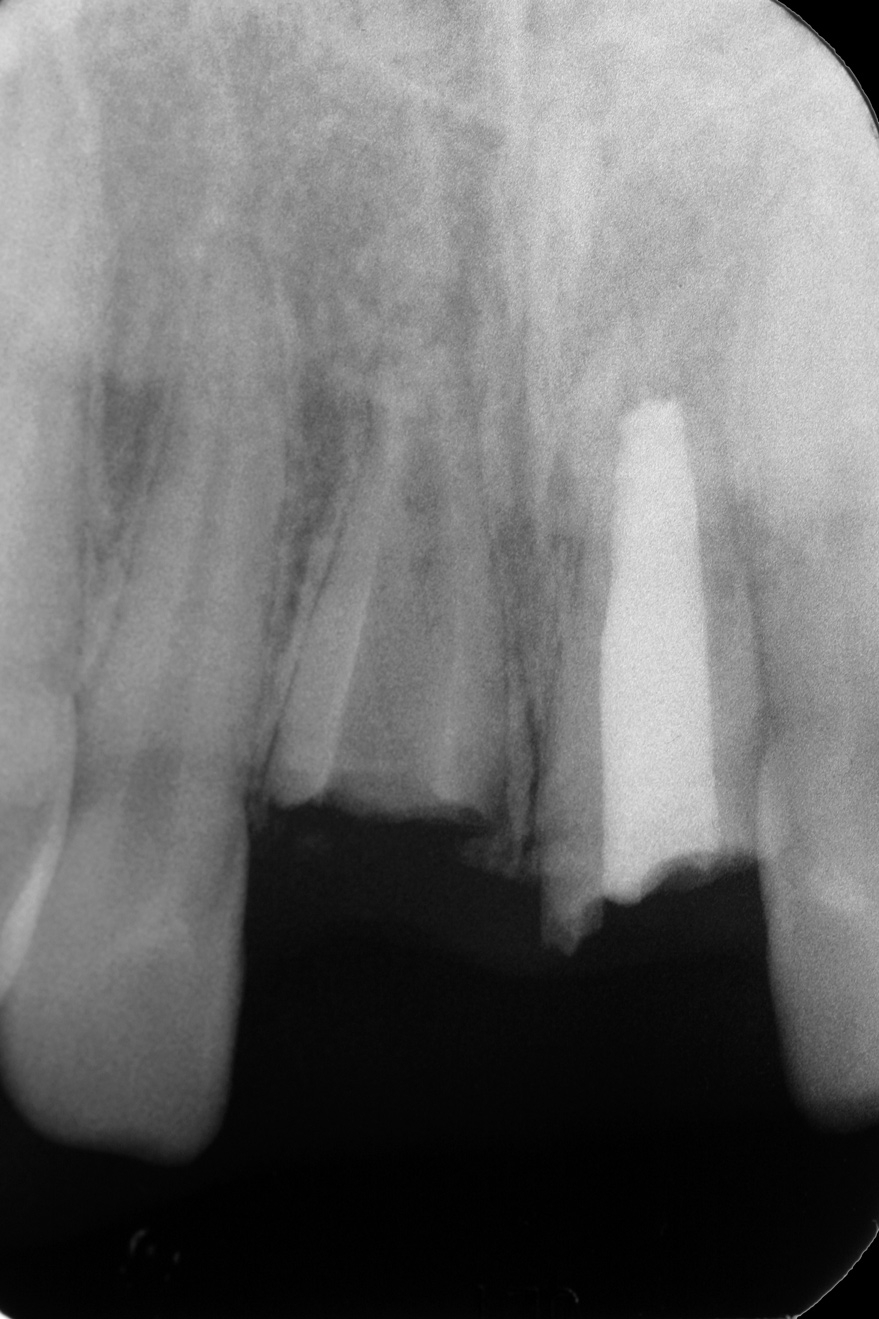

The patient returned 4.5 years later, at age 14, for evaluation of his right central incisor. The tooth was now approximately 2.5 mm in infraocclusion (Figure 14). He was asymptomatic, with neither tooth No. 8 nor No. 9 tender to percussion or palpation. No. 9 had normal mobility and the PDL appeared intact radiographically. The radiograph showed No. 8 to have extensive replacement resorption of the root. Gutta-percha was exposed from the mesial CEJ around the apex and down the distal aspect of the root, leaving a sliver of coronal root about 4 mm in length attached to the distal CEJ (Figure 15).

Fig 15. Age 14. Radiograph revealed extensive replacement resorption of tooth No. 8.

Figure 15

Fig 16. Age 14.5. Radiograph of the remaining root immediately after decoronation.

Figure 16